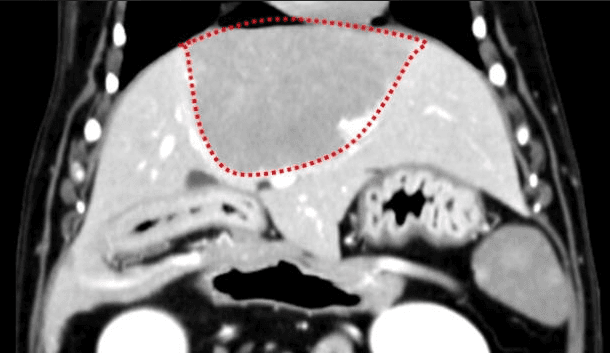

간, 담도 수술은 수술뿐만 아니라, 수술 후 중환자 관리도 중요하기 때문에 외과와 내과의 협진이 매우 중요합니다. 동탄시티동물의료센터에서는 최신 수술 장비의 도입으로 간담도 수술에서 출혈 및 부작용을 최소화 하였으며, 수술 후 협진 시스템을 통해 수술 후 관리에도 최선을 다하고 있습니다.

간종양

동탄 1 신도시 최초 Aquilion CX/128 slice CT를 동물병원에 도입하였습니다. 최고 사양 CT 모델 Aquilion CX/128 slice를 활용하여 0.5 mm의 얇은 128개의 단면 영상을 신속히 획득 할 수 있어 마취 시간을 단축시킬 수 있습니다. 또한, 128 슬라이스의 고화질의 CT 영상을 통해 영상 왜곡을 최소화하고 X-ray에서는 확인하기 힘든 5 mm 이하의 미세 병변도 확인이 가능하여 정확한 진단을 할 수 있습니다. 심화 진단이 필요한 경우, 조영제 인젝터를 통한 동맥기 촬영으로 종양 유래 확인, 간 질환 진단, 심혈관계 진단이 용이합니다. 저희 동탄시티동물의료센터에서는 본원 환자뿐 아니라 1차 동물 병원과의 CT 촬영 의뢰 시스템을 통해서 원활한 협진이 가능하도록 최선을 다하고 있습니다.

0164 채널 CT 촬영을 통해서 신속하게 고화질 영상을 얻어, 종양 유래 확인 및 전이 평가, 간문맥단락증(PSS), 선천적 뼈 기형과 같은 심화된 진단을 할 수 있습니다.